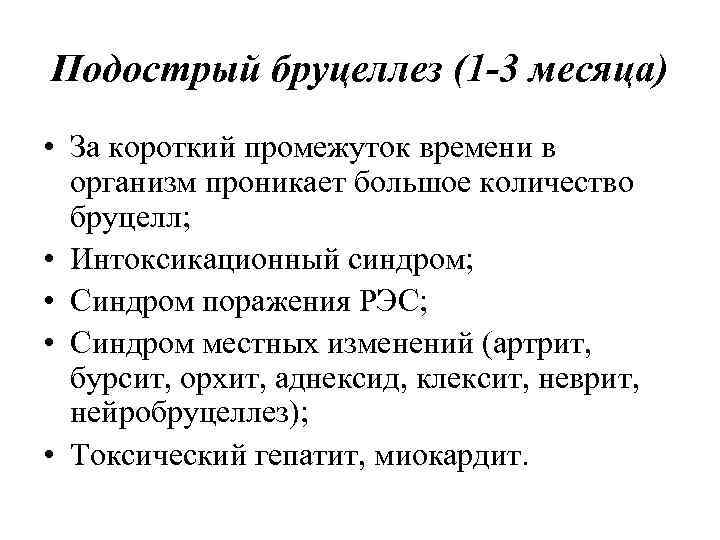

Подострый бруцеллез (1 -3 месяца) • За короткий промежуток времени в организм проникает большое количество бруцелл; • Интоксикационный синдром; • Синдром поражения РЭС; • Синдром местных изменений (артрит, бурсит, орхит, аднексид, клексит, неврит, нейробруцеллез); • Токсический гепатит, миокардит.

Подострый бруцеллез (1 -3 месяца) • За короткий промежуток времени в организм проникает большое количество бруцелл; • Интоксикационный синдром; • Синдром поражения РЭС; • Синдром местных изменений (артрит, бурсит, орхит, аднексид, клексит, неврит, нейробруцеллез); • Токсический гепатит, миокардит.